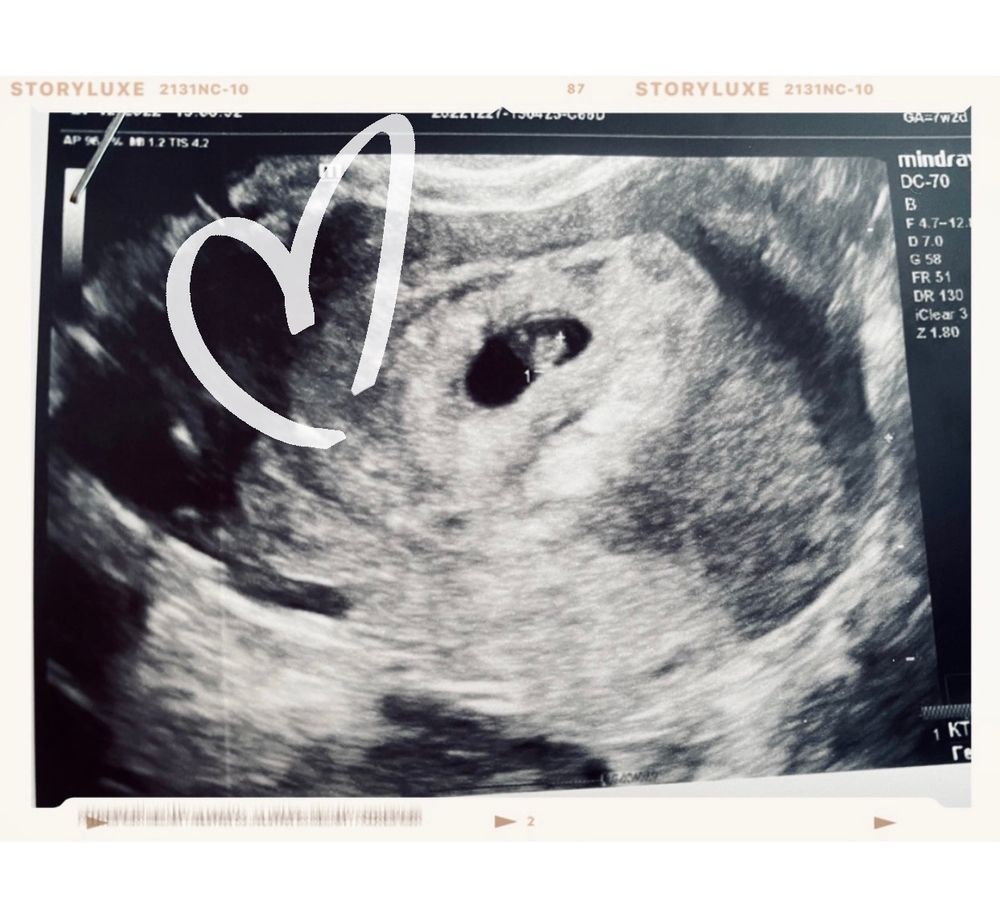

Второе узи🥰

Уже 8 недель! как быстро идет время. Малыш растет, сердечко 120 ударов❤️